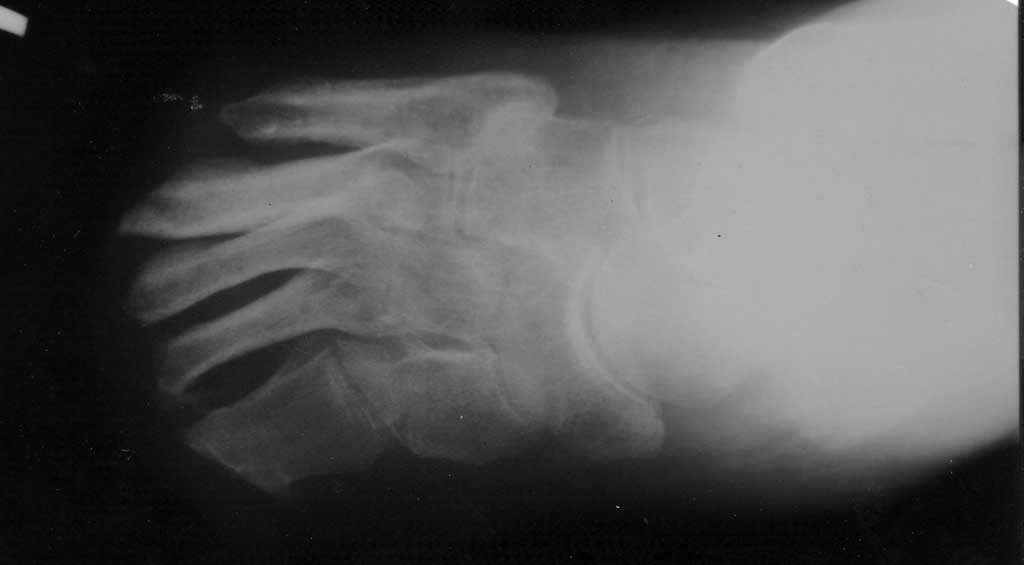

Вложение не в текстовом формате было извлечено…

Имя     : УЛБОЙТПЧБОЙЕ.jpg

Тип     : application/octet-stream

Размер  : 25537 байтов